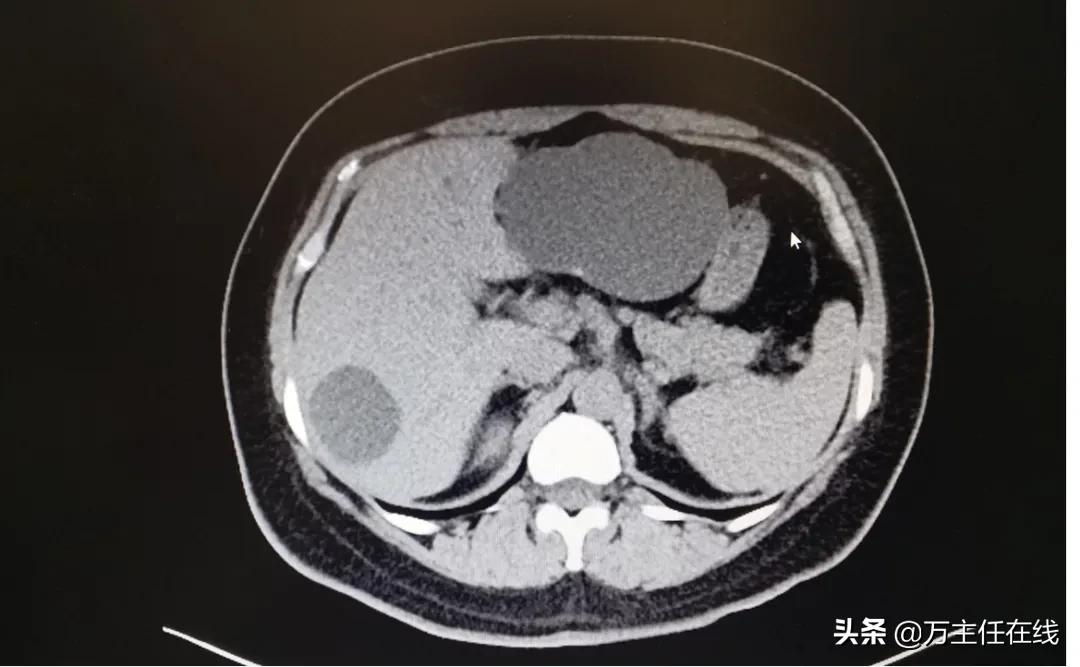

图表 1双侧肝囊肿

陈女士今年五十多了,当从CT中看到2块大的囊肿,得知自己需要手术的时候,对术后留下的疤痕产生了担忧:“切这么大的东西,那要留好长的疤吧”。“我们是从人体自然通道,也就是消化道进入,不会留下疤痕,且对身体负担很小。”消化内镜中心的万荣主任如是说。